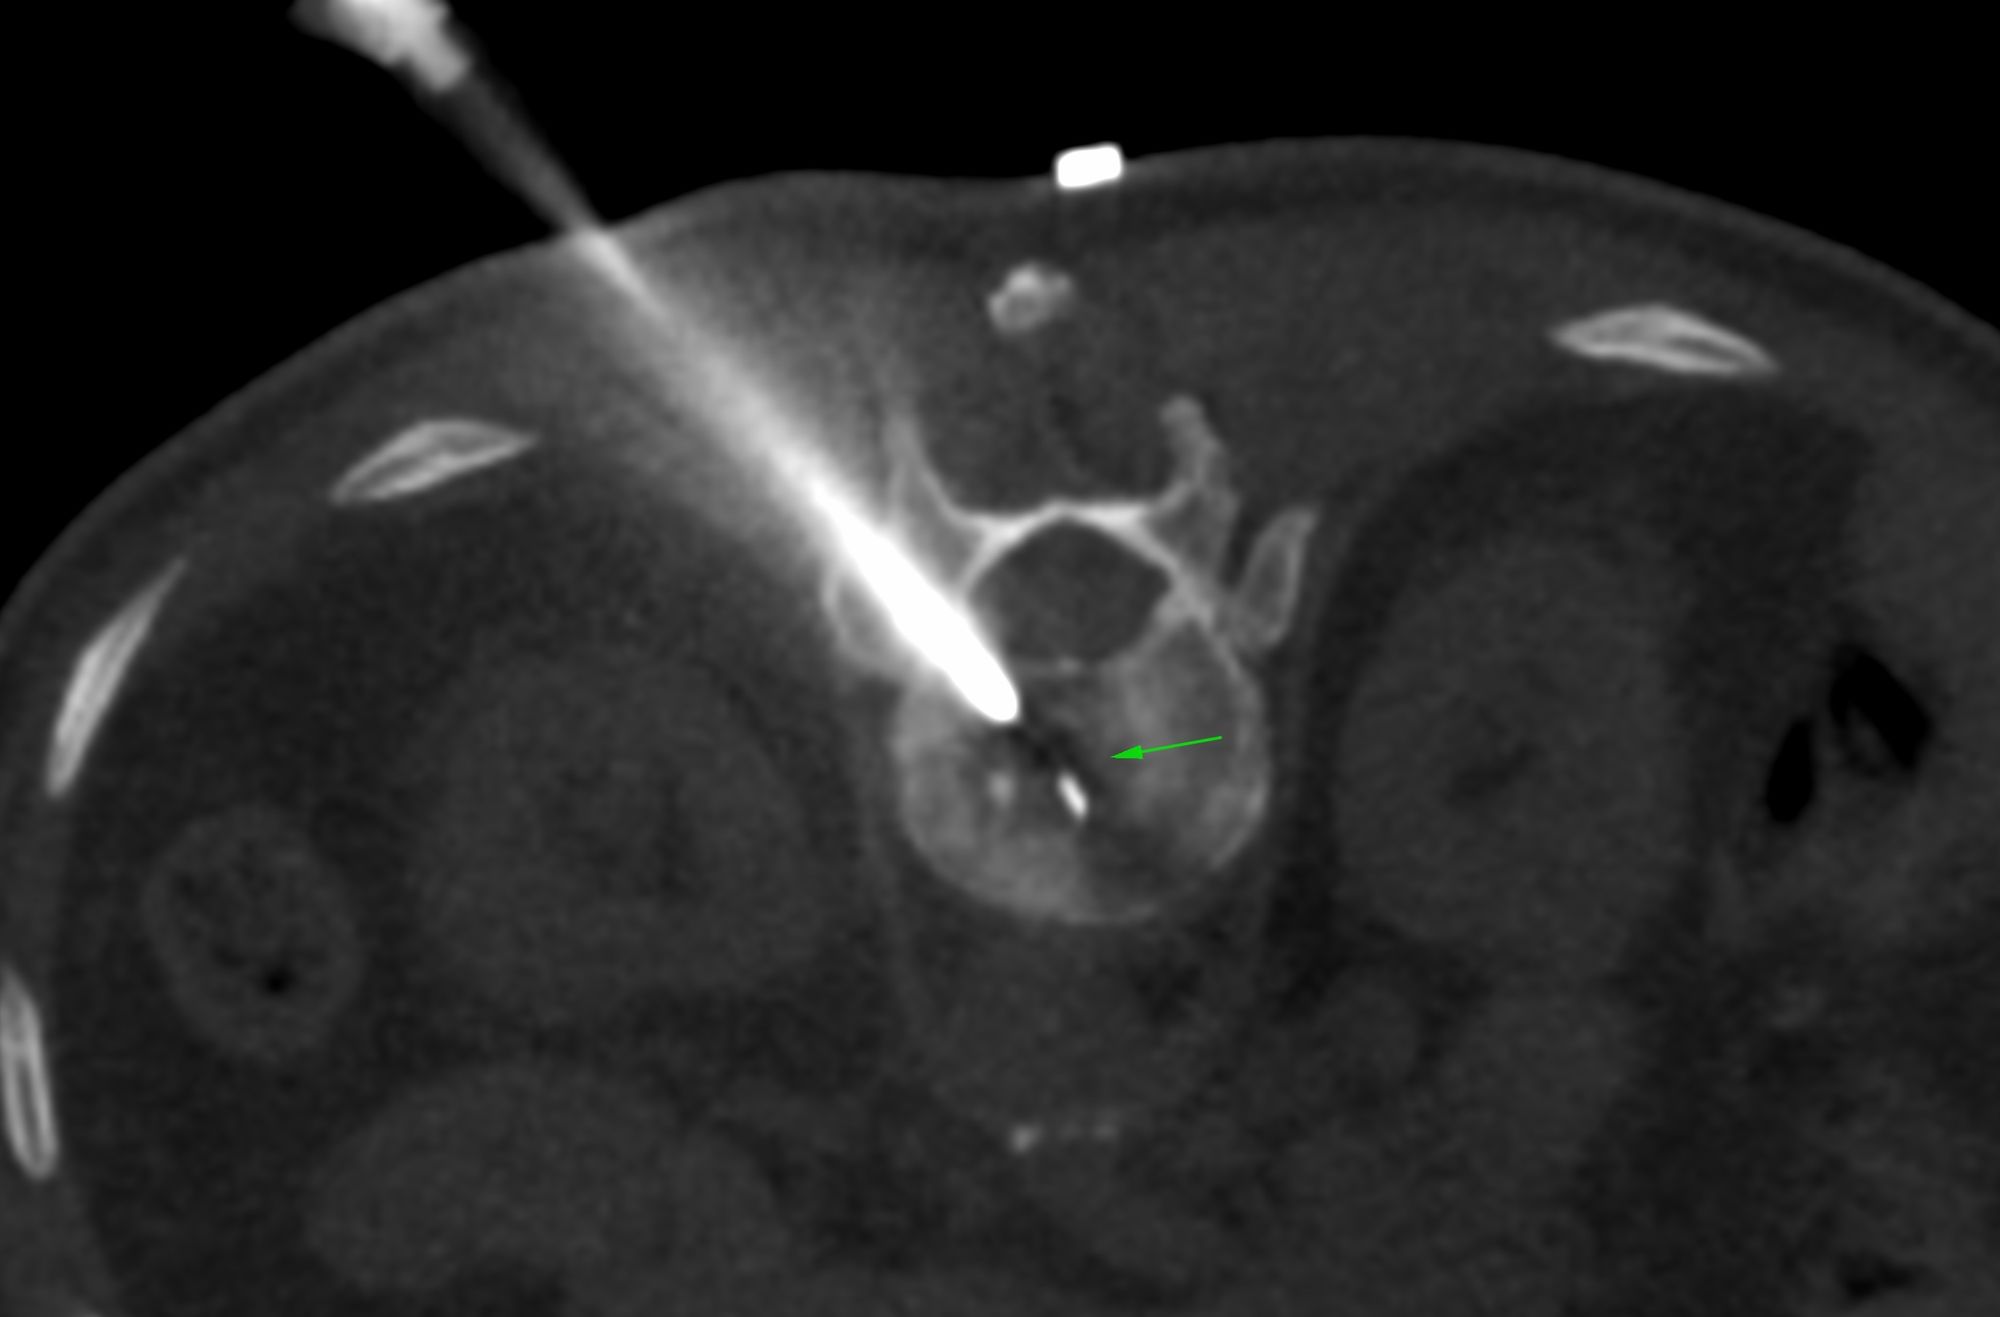

Case 47: Ovarian Mass Biopsy - Serous Adenocarcinoma

Bhavin Jankharia - 08 July 2021